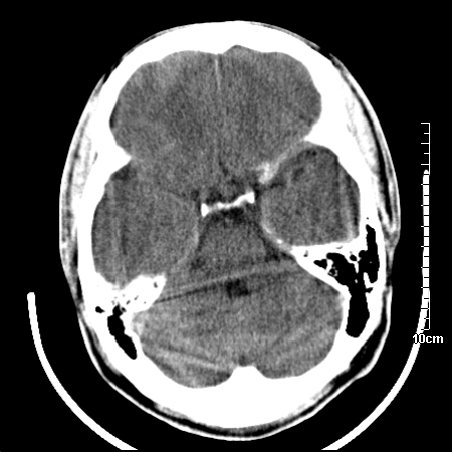

4天上述症状加重伴左侧肢体发软,复查ct,

病人在家输液时出现发热.头痛.恶心等不适

右侧放射冠区混杂密度灶,边缘不清,病人较年轻,结合有发热病史,支持感染性病变,建议密切结合临床可抗感染治疗后复查。

右侧颞叶病变定性困难,既然发病急,又有发热,脑脓肿不能除外。

右侧颞叶混杂密度灶,强烈建议:增强ct检查